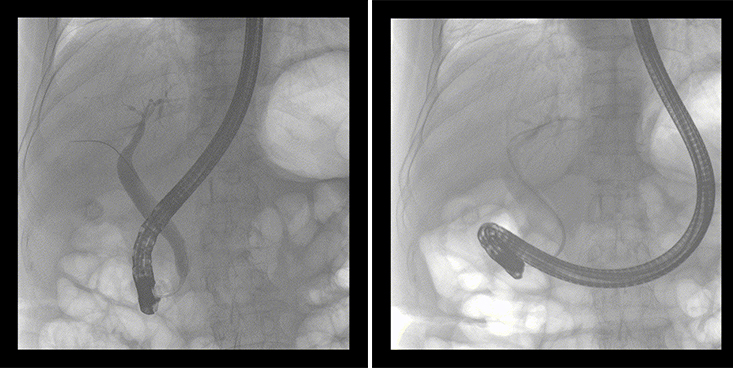

一位86歲的女性患者近來出現(xiàn)腹痛,入院后CT檢查并結合臨床表現(xiàn)被診斷為急性膽囊炎伴膽囊結石。經專家團隊協(xié)商并與患者家屬溝通,決定對患者實施經內窺鏡逆行胰膽管造影(ERCP)。

ERCP(經十二指腸鏡下逆行胰膽管造影)現(xiàn)已成為比較成熟的微創(chuàng)介入技術,被廣泛的應用于臨床,ERCP也是消化內鏡領域難度大、風險大、技術復雜的微創(chuàng)手術,其并發(fā)癥多為致命性,ERCP手術對醫(yī)生的要求很高,因此,ERCP醫(yī)生又被稱為“刀尖上的舞者”。因為手術難度較大,過程復雜,需要C形臂精準的配合,對影像清晰度的要求也非常高。

普愛醫(yī)療移動式平板中C為本次ERCP手術提供實時無損高清影像,幫助醫(yī)生精準定位?!俺上裥Ч浅0簦⊥耆惠攪H大牌的醫(yī)學影像設備……”鼓樓醫(yī)院江北國際醫(yī)院內鏡中心手術團隊對普愛醫(yī)療移動式平板中C的成像效果給與了高度的評價。

在消化內科主任的領導和多科室全力配合下,南京鼓樓醫(yī)院江北國際醫(yī)院成功完成了首例ERCP手術。